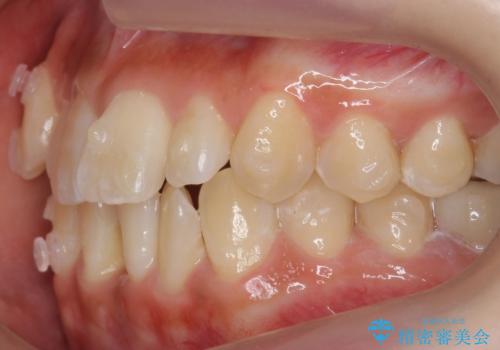

八重歯 インビザラインで抜歯矯正 ただし1本のみの抜歯で済みます

今回は口元も出ていないうえに、右上のみの八重歯のため奥歯を後ろに下げて治療しました。

ただし、下の前歯は入りきらない為1本のみ抜歯しています。

右上の犬歯をおろしてくるのに、顎間ゴムを使用しています。